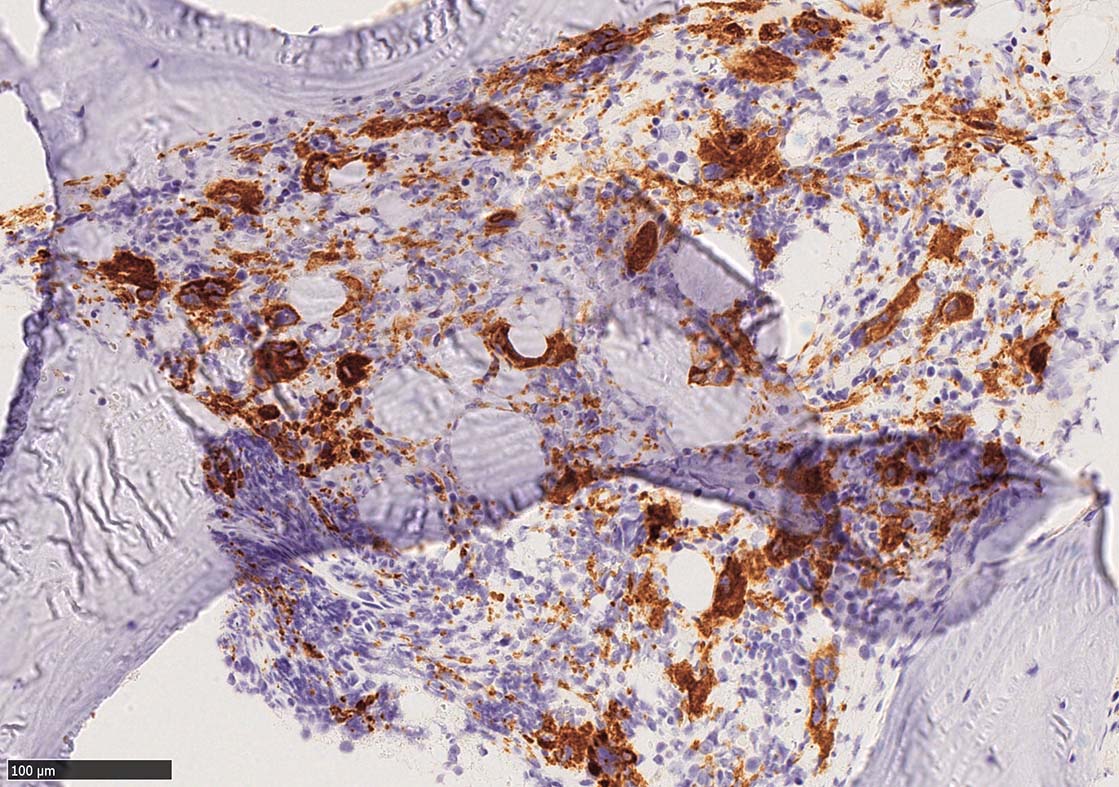

塗銀染色

CD42b染色